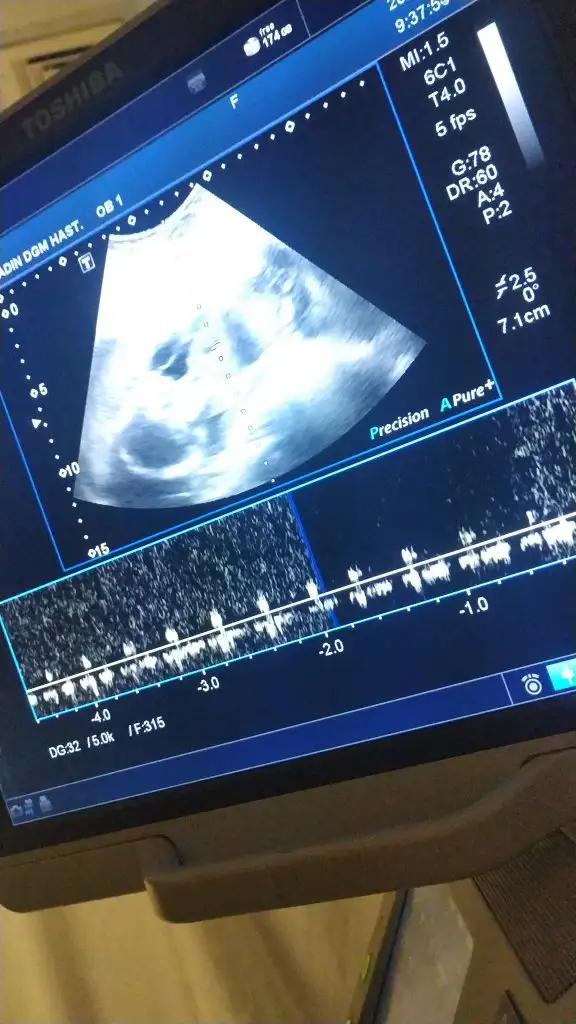

Bebişimi gördüm.

Kızlar çok şükür muanem güzel geçtii

Bebişlerini biri 365gr

Diğeri 351gr

Boy olarak kg olarak çok yakınlar, doktor güzel toparlanmışlar dedi subhanallah

Artık kemiklerini bile gördümçok farklı bişey ya

dr hamur işi ve abur cubur tüketme seni şişirmesin zorlanırsın dedi. Hamile kaldığımdan beri 8 kg almışım

Haftaya pazartesi detaylı var bakalım o nasıl geçecek hayirlisi inşallahdarısı sıradaki annelerin başına inşallah